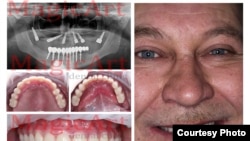

“Diş və kosmetik əməliyyat daha çox populyardır, çünki onların heç də hamısının Avropada tibbi sığortası yoxdur”, – Uladzislau Androsau deyir. “Məsələn, diş implantasiyası, döş implantasiyası... bu kimi əməliyyatların 70 faizi gəlmə müştərilərimizin istəyi əsasında aparılır”, – o əlavə edir.

İmplant dişlər

“Biz Baltikyanı ölkələr üçün, xüsusilə, burdakı kimi, orda da iki dəfə baha olan diş implantasiyası bazarı yaradırıq. Eyni zamanda, Latviyada, məsələn, diş implantasiyası Skandinaviyadan və ya Britaniyadan iki-üç dəfə ucuzdur”, – Androsau deyir.

Diş implantasiyanın qiymətləri də kəskin fərqlənir. Belarusda yeni dişin qiyməti 550 dollardısa, ABŞ-da bu rəqəm 2 min 500 dollardır. Belarusa gələn bəzi turistlər dörd, ya beş yeni diş qoydururlar.